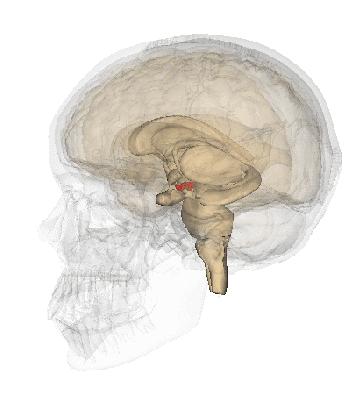

颅骨

脑部

脑干

脑室系统